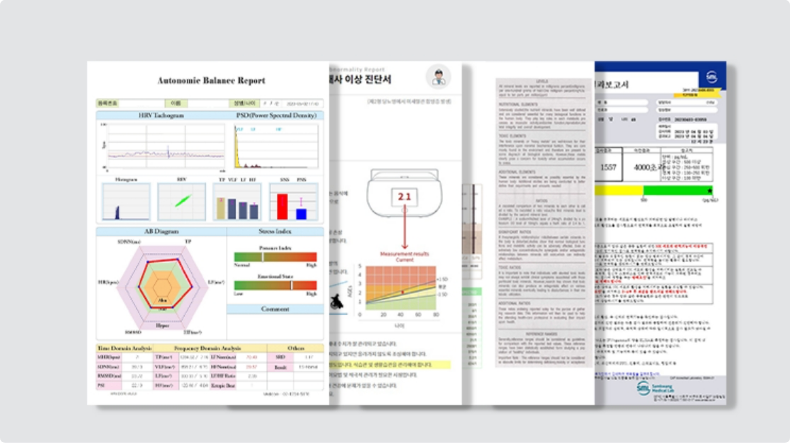

피부과전문의가 답변하는

자주 묻는 질문

-

항노화 효과를 기대할 수 있나요?

텔로미어(Telomere)는 세포분열에 관여하는 염색체로 세포 시계의 역할을 담당하며 유전자의 조각들로 염색체의 끝부분을 막아 완충 역할을 합니다. 그러나 세포분열이 반복될수록 텔로미어의 길이가 점점 짧아지며, 이는 노화와 밀접한 연관이 있습니다.

고압 산소치료는 텔로미어의 길이를 유지하거나 늘리는 것은 노화를 늦추는 효과가 있어, 지속적인 고압 산소치료는 염색체의 텔로미어를 연장시켜 항노화 치료에 도움이 됩니다.

-

시술 및 수술 후 회복에 도움이 되나요?

혈액순환의 활성화로 부종이나 멍 회복에 도움이 됩니다

-

새로운 혈관도 생성이 되나요?

기압을 높이면 적혈구와 결합하지 않아도 산소 분자 그대로 혈액 속으로 녹아들어 모세혈관과 세포까지 활성화되어 새로운 혈관들이 생성될 수 있는 환경을 조성합니다

왜 보스피부과를

선택해야 하나요?